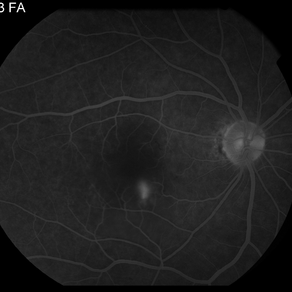

AMPPE

Apr 29 2014 by David W. Faber, MD

24-year-old female presented with central blurry vision for 3-5 days. Vision : OD 20/20, OS 20/100

Photographer: Jodi Schiele, Rocky Mountain Retina Consultants, Salt Lake City, Utah

Condition/keywords: acute multifocal placoid pigment epitheliopathy (AMPPE)